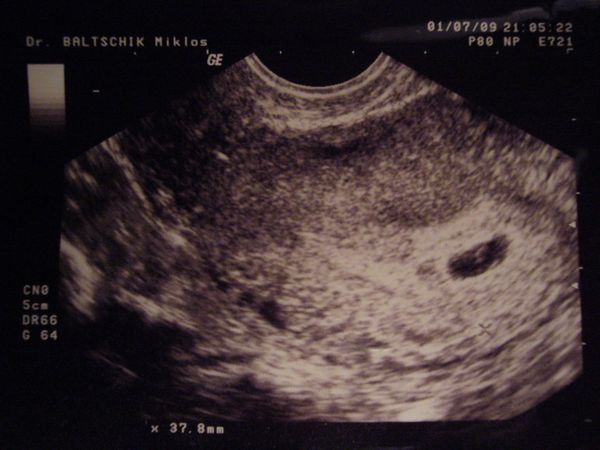

Aki pedig mostanában megy UH-ra annak drukkolok, hogy minden rendben legyen és esetleg a neme is kiderüljön

Tőlem ma reggel levették a vért az AFP-hez, holnap délre kész az eredmény, aminek nagyon örülök, mert a nőgyógyászhoz hétfőnként lehet menni, így nem kell várnom plusz egy hetet, pár nap és mehetünk kukucskálni

Már nagyon várom, remélem, minden OK odabent. És ha magamutogatós a kicsike, talán az is kiderül, mije van a lába között, de ha nem, az sem baj